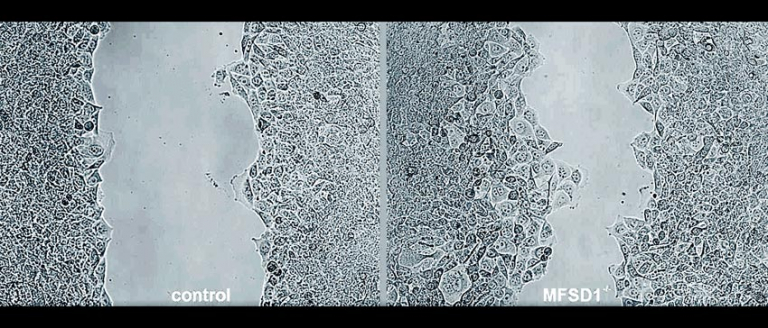

截图来源:eurekalert网站相关视频

MFSD1是哺乳动物中的一种蛋白质。研究小组在小鼠体内制造了缺乏这种蛋白质的癌细胞。没有这种蛋白质,癌细胞的移动速度要快得多,这表明MFSD1阻止了癌细胞的移动。研究人员在患有乳腺癌、结肠癌和皮肤癌的活小鼠身上进行了测试,结果表明,在缺乏MFSD1的情况下,转移率有很大的增加。